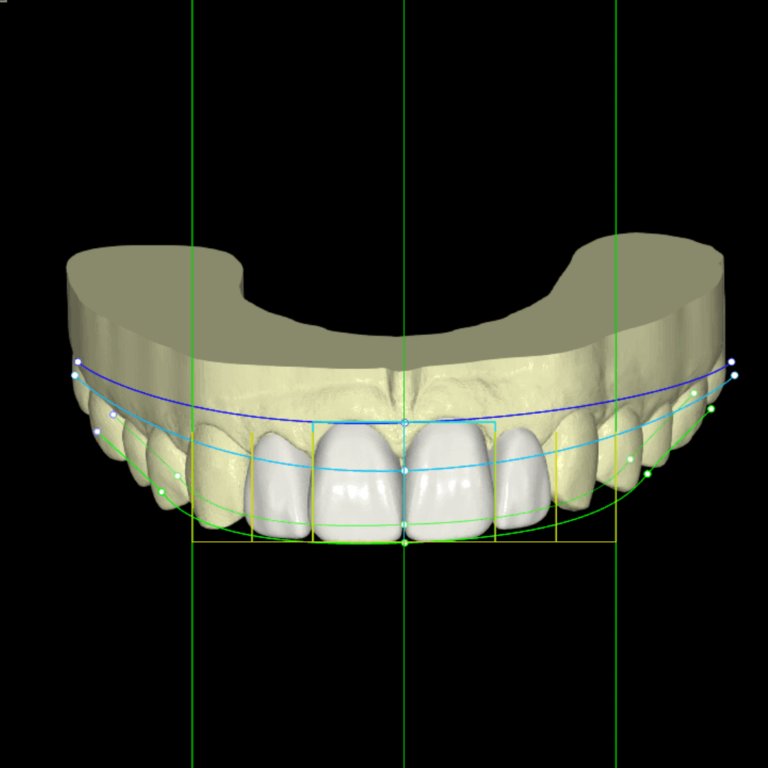

- Smile Design

- Surgical Implant Guides

- Supporting Digital Workflows for Intra-oral Scanning